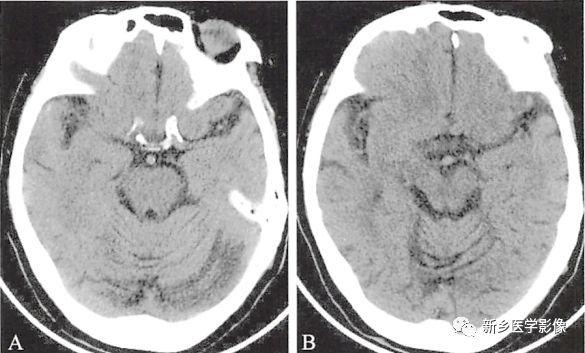

两种常见脑萎缩ct表现